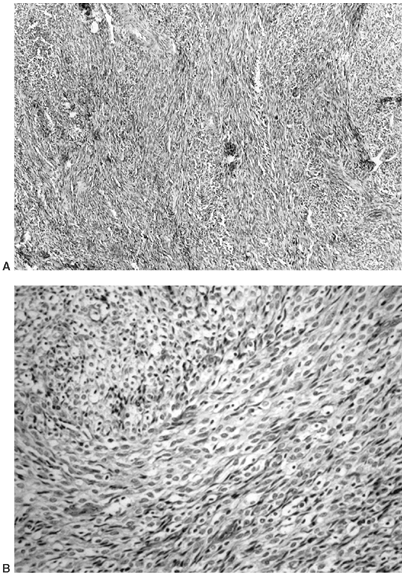

Figure 14.9 A:

Typical histologic appearance of an osteoblastic osteosarcoma. There is immature bone being formed from cells that vary in size, shape, and amount of nuclear material. These findings are typical of malignant cells (10 × magnification) B: Higher magnification (40 ×) of the osteosarcoma in (A). The nuclear detail is more clearly seen, and the bone seemingly coming directly from these bizarre cells makes the diagnosis of an osteosarcoma. |